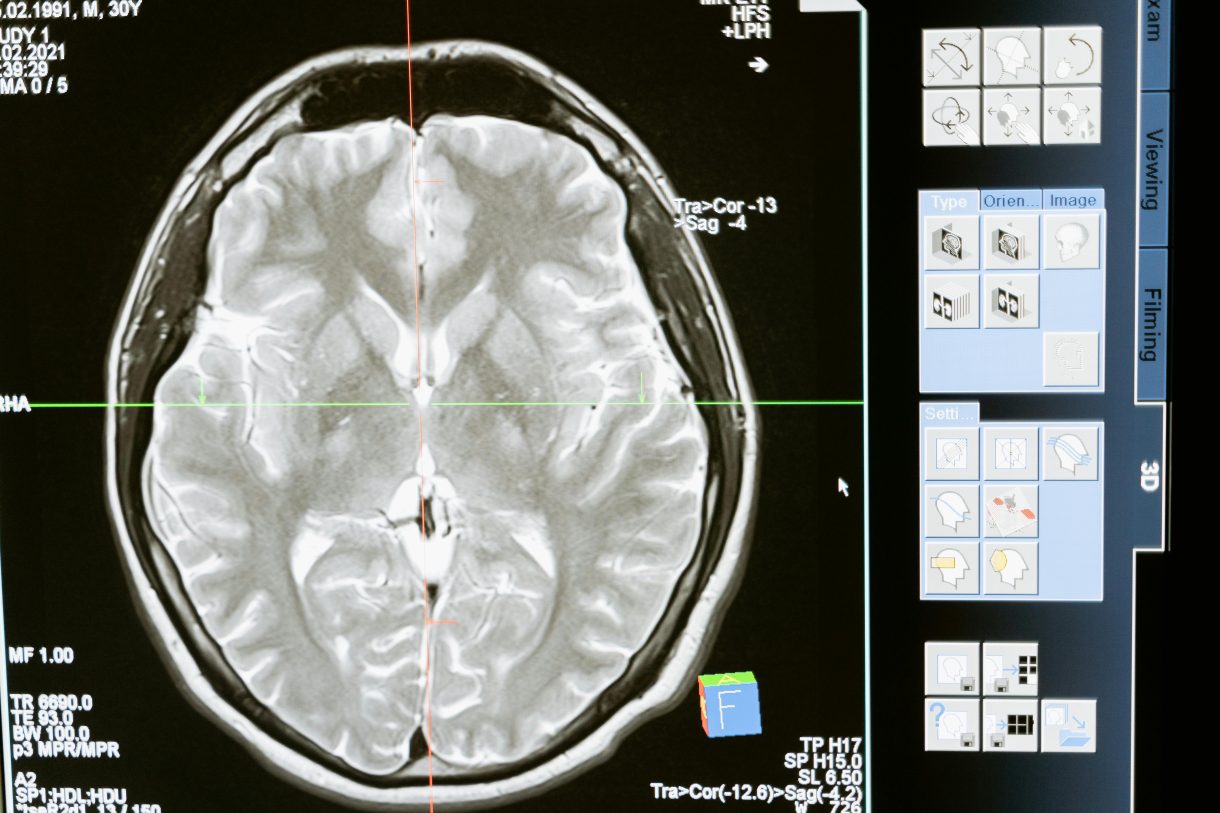

Un paciente tetrapléjico en Shanghái ha logrado jugar videojuegos con la mente tras un implante cerebral colocado en marzo de 2025. Se trata del primer ensayo clínico de interfaz cerebro-computadora invasiva en China, realizado por el CEBSIT. En solo tres semanas, el paciente pudo controlar juegos de carreras y ajedrez sin usar sus extremidades. China entra así en la carrera global de la neurotecnología, rivalizando con Neuralink de Elon Musk.

China ha implantado con éxito el dispositivo de control cerebral más pequeño del mundo: 26 mm de diámetro, 6 mm de grosor. Es un avance técnico extraordinario en la naciente industria de interfaces cerebro-computadora (BCI), que busca conectar el cerebro humano directamente con dispositivos digitales.

El dispositivo fue desarrollado por el Centro de Excelencia en Ciencia Cerebral y Tecnología de la Inteligencia (CEBSIT), y se basa en una arquitectura de electrodos neuronales ultraflexibles, 100 veces más delgados que un cabello humano. Esta estructura permite detectar señales neuronales con alta fidelidad, sin provocar reacciones inmunológicas ni dañar el tejido cerebral.

Cada electrodo está equipado con 32 sensores microscópicos, capaces de registrar la actividad eléctrica de múltiples neuronas a la vez. El resultado es un flujo constante de datos cerebrales, con suficiente precisión para traducir intenciones mentales en comandos digitales con una sorprendente velocidad de adaptación.